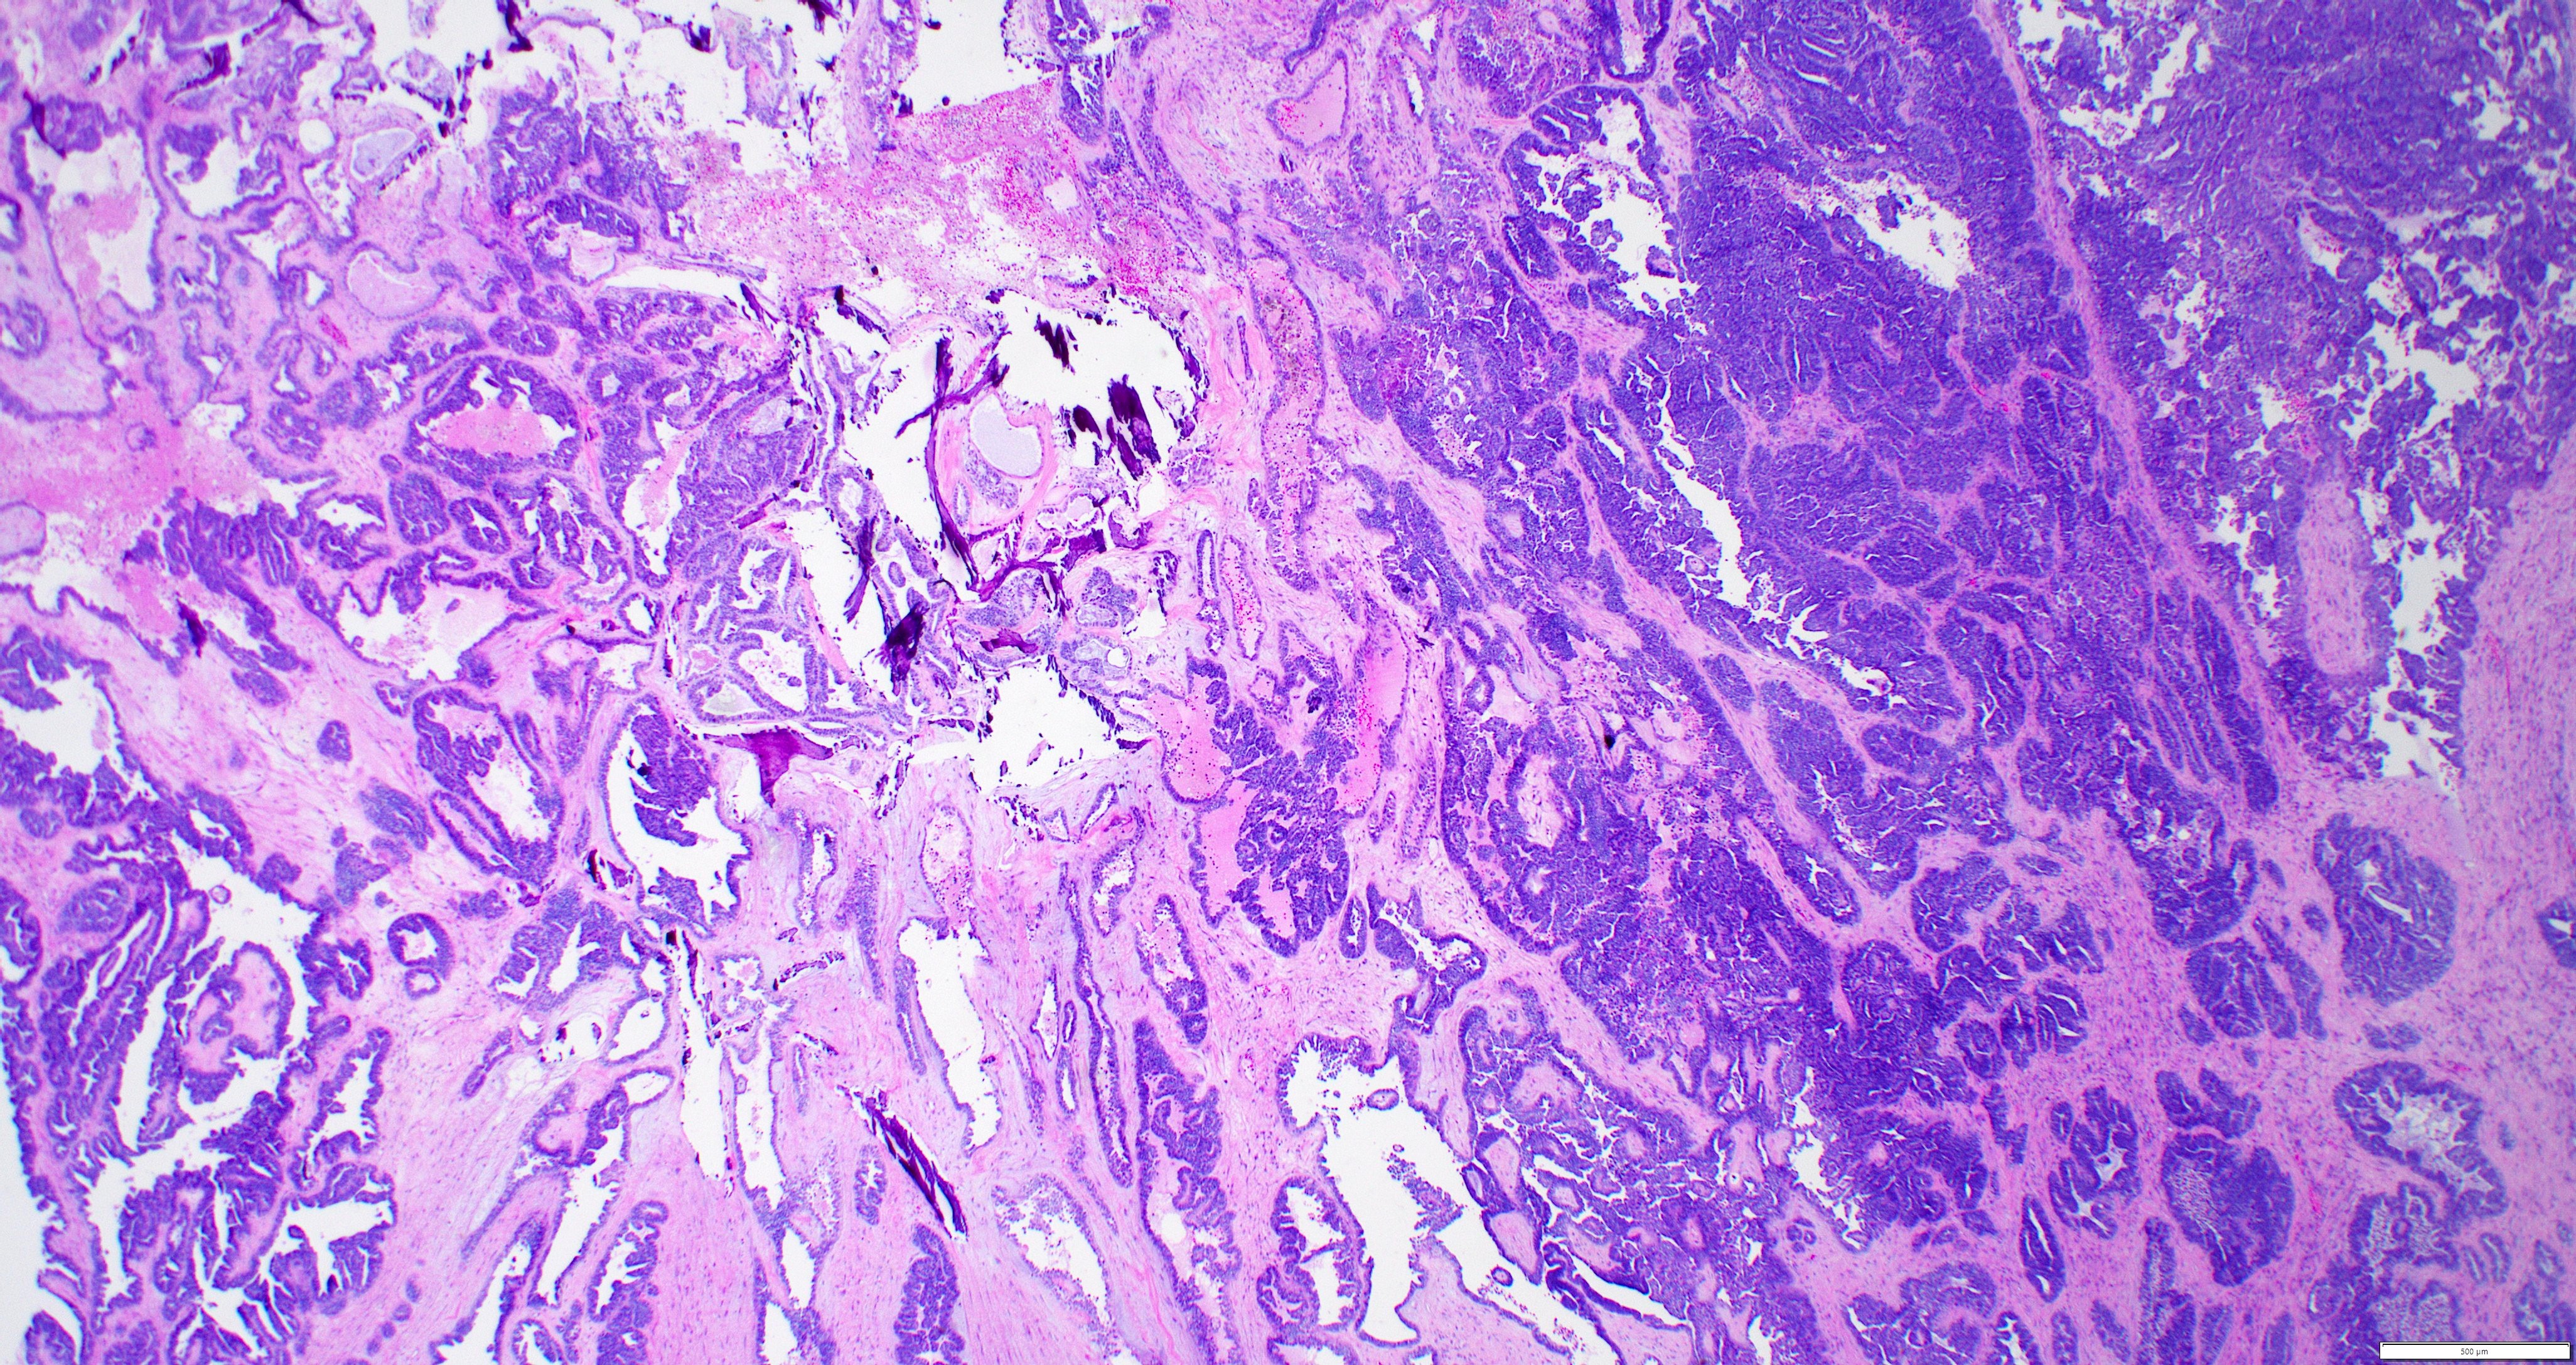

- Variety of histologic patterns that may be present within the same tumor

- Most frequently small tubules with ductal / glandular growth

- Papillary, solid growth, trabecular, retiform, sex cord-like, sieve-like, glomeruloid and spindle cell areas have all been described

- Luminal eosinophilic secretions are characteristic but not always identified

- Tumor cells can be flattened, cuboidal or columnar with mild to moderate cytological atypia

- Clear cell features can be seen but are less common

- High grade cytological atypia is usually not a predominant feature

- Nuclei show vesicular chromatin and nuclear grooves

- Sarcomatoid transformation has been seen in rare instances

- Squamous, ciliated or mucinous differentiation (metaplasia) are not present and there are no associated mesonephric remnants (J Clin Med 2021;10:698)

Microscopic (histologic) images

Contributed by Daniel Graham, M.D., Adele Wong, M.B., B.Ch., B.A.O. and Lucy Ma, M.D.